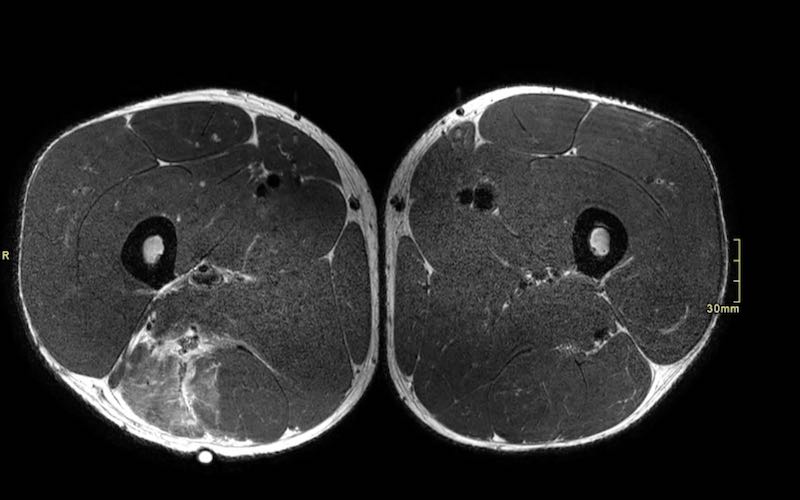

Trên các hình ảnh axial này, có thể thấy tăng tín hiệu và dày lên của gân cơ nhị đầu đùi bên trái (vòng tròn chấm vàng) khi so sánh với bên không bị tổn thương (vòng tròn chấm trắng).

Tại đây bạn có thể cuộn qua các hình ảnh axial. Có thể phóng to hình ảnh bằng cách nhấp vào chúng.

Đây là tổn thương bán phần, bắt đầu từ gân chung ở phía gần, bao gồm cả vùng MTJ và gân trong cơ ở phía xa hơn. Chiều dài vùng phù nề và mức độ biến dạng gân đều ở mức độ cao. Trường hợp này được phân loại là tổn thương BAMIC 3b/c.